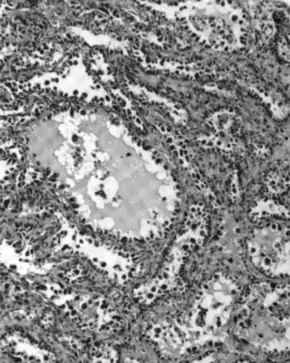

Most people with epithelial ovarian carcinoma, about two-thirds, have a serous carcinoma,[21] though this proportion is estimated as high as 80%.[24][49] Low-grade serous carcinoma is less aggressive than high-grade serous carcinomas, though it does not typically respond well to chemotherapy or hormonal treatments.[21] Serous carcinomas are thought to begin in the Fallopian tube.[48] Histologically, serous adenocarcinomas have psammoma bodies. Low-grade serous adenocarcinomas resemble Fallopian tube epithelium, whereas high-grade serous adenocarcinomas show anaplasia and nuclear atypia.[22]

Serous tubal intraepithelial carcinoma (STIC) is recognized to be the precursor lesion of most ovarian high-grade serous carcinomas.[50] STIC is characterised by

- Abnormal p53 staining

- Ki67 proliferation index in excess of 10%

- Positive WT1 (to exclude metastases)[51]